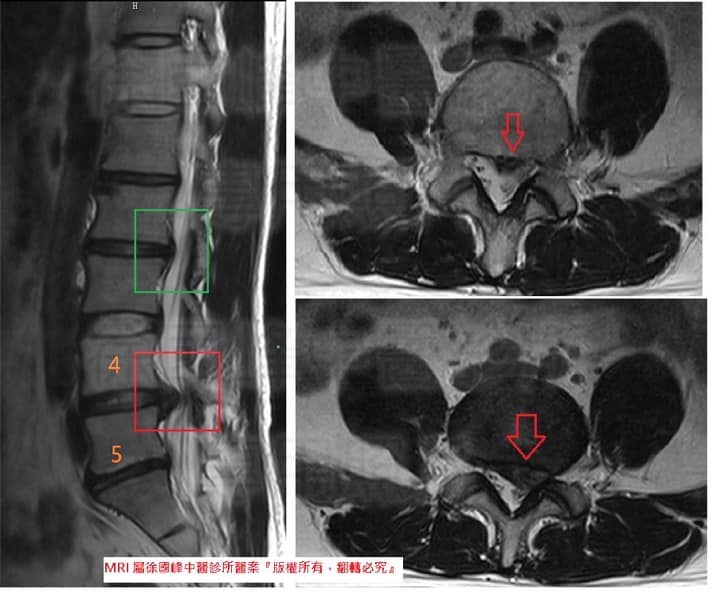

👨⚕️徐醫師看過MRI後,從骨科及神外的角度來說,這是巨大椎間盤突出通常都需安排手術,但患者目前突出還未壓到馬尾神經,也未出現大小便失禁的問題,所以徐醫師認為還有機會能不通過手術的方式來治療,除了積極治療外還要加上專屬復健運動來做輔助,所以雙方都要很努力才能一起度過難關

1.左側L4L5 巨大椎間盤突出